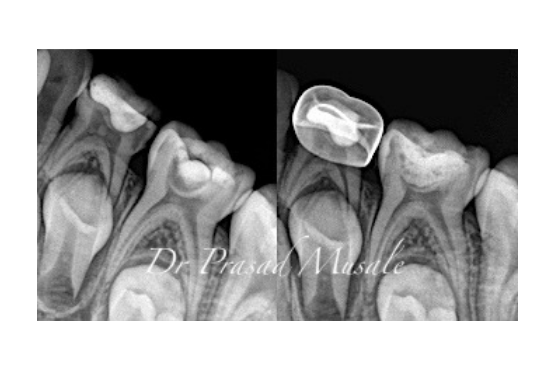

When your child’s cavity is deep but the nerve is still sound inside, we remove the decay, place a therapeutic cement and restore the tooth in function.